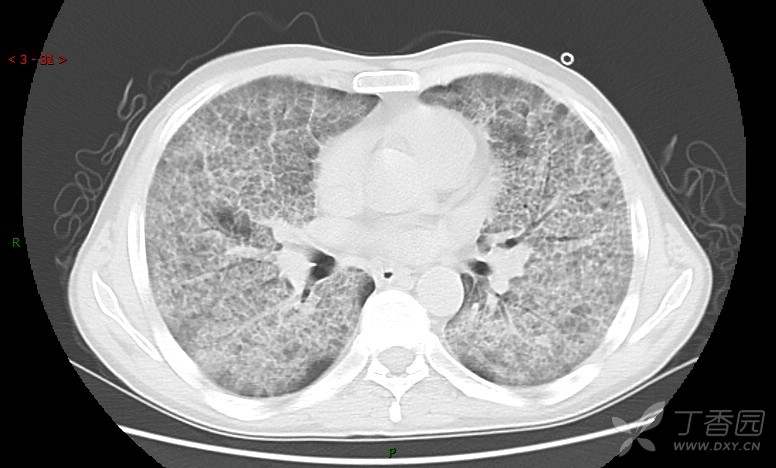

地图+铺路石征=PAP?那升高的CEA怎么说(病例3连发,附其他2例链接)

患者男,42岁,咳嗽半年余,加重伴憋喘2月余。

肺内弥漫性网状结节影,PET-CT却无阳性病灶,这是?(附其他2例链接)